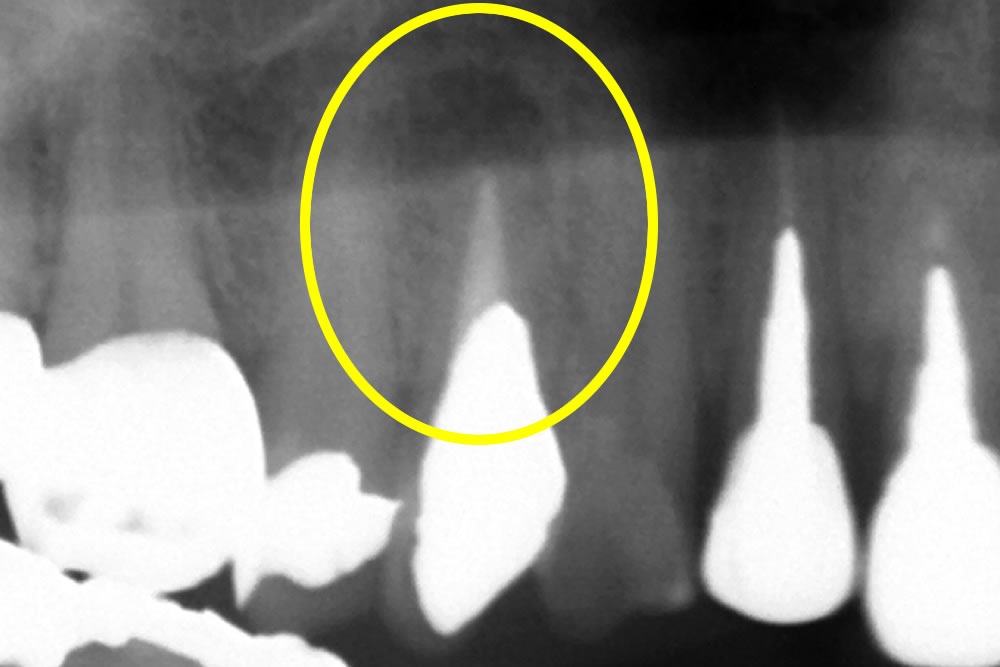

レントゲンで見ると、過去に根の治療が施されていますが、 根の先に黒い影が見えます。

詰め物を除去して、顕微鏡にて確認して見ると、本来治療するべき神経の穴とは別のところに穴が開いてしまっていました(パーフォレーション)。虫歯で開いてしまう事もありますが、治療の偶発症として開いてしまう事もあります。本来の神経の穴ではないので、特殊なセメントを使用して封鎖しました。